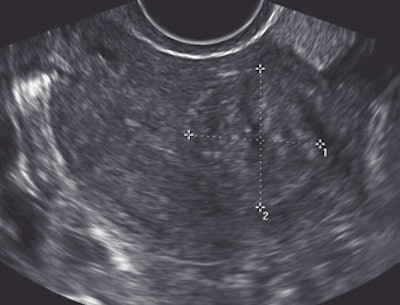

| A 40-year-old woman with a fibroid. Above, transverse view of uterus shows fibroid (calipers). Exact location of fibroid with respect to uterine cavity is unclear because posterior aspect of fibroid obscures side of endometrium. Below, coronal view shows that fibroid is not submucous, but is intramural without distorting shape of uterine cavity. Plane shown here was deemed by radiologist to be best plane to show closest relationship between fibroid and endometrium, showing that the fibroid did not extend into cavity but just abuts it. Benacerraf B, Shipp T, Bromely B, "Which Patients Benefit from a 3D Reconstructed Coronal View of the Uterus Added to Standard Routine 2D Pelvic Sonography?" (AJR 2008; 190:626-629). |